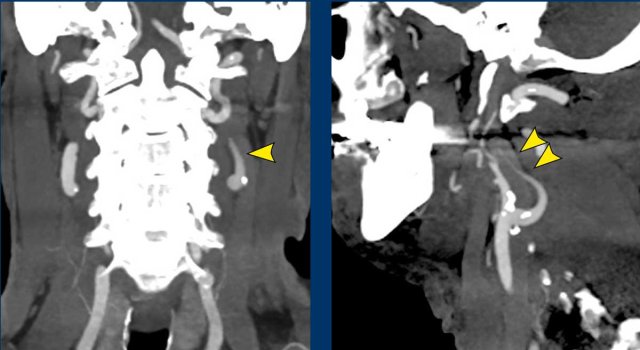

Images

• When you compare the right and left submandibular gland (image 1), you will notice an enhancing mass lesion on the right (arrow on scroll image).

• The enhancement can be followed on image 2 and 3 along the internal and the external carotid

• This can also be appreciated on the sagittal image, where the enlarged gland is seen (*) and streaks of enhancement along the internal carotid artery (arrow heads).

Seven months later the tumor surrounding the ICA and ECA has enlarged.

Conclusion

This turned out to be an adenoid cystic carcinoma with perineural tumorspread.

On the TWIST MRA there is early artery enhancement in the large lesion on the right.

Notice that on the left side there is also a early arterial enhancing lesion on the carotid bifurcation.

Bilateral paraganglioma.

Bilateral lesions are common in inherited syndromes like SDH gene mutations.

Here a companion case with a paraganglioma on the left.

Continue with the Twist-MRA images...

Image

3D-TWIST MRA shows intense early arterial enhancement

The illustration shows the level of obstruction of the postganglionic neuron.